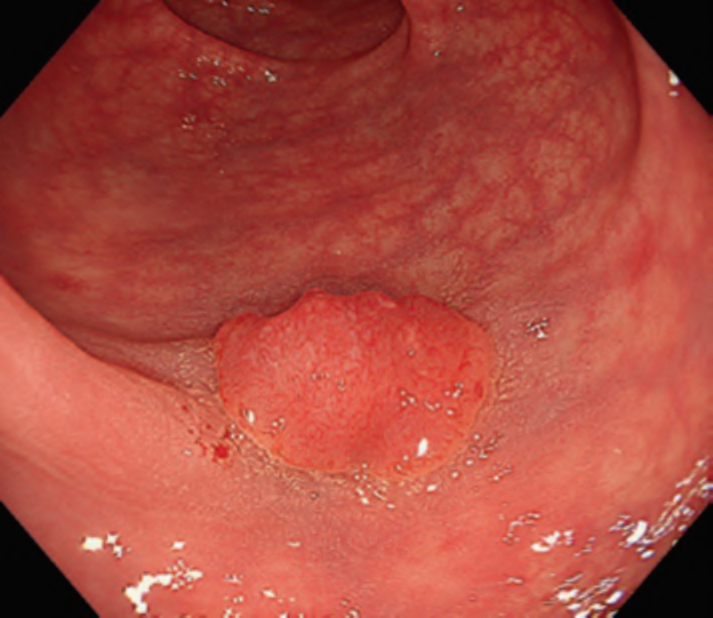

First, research on AI for the diagnosis of cancer depth has taken precedence, given its greater clinical importance. Tamai et al. developed a CADx for diagnosing invasive cancers (requiring surgical resection) using magnifying NBI images, reporting a sensitivity of 83.9% and specificity of 82.6% [30]. Takeda et al. also reported a correct diagnosis rate of 94.1% for invasive cancers using CADx for endocytoscopy (EndoBRAIN-Plus) [31]. . Figure 2 shows an early-stage colorectal cancer (T1) that diagnosed using the EndoBRAIN-Plus. Tokunaga et al. created a more versatile and practical CADx system, capable of determining whether the target lesion can be treated endoscopically, based on white light images [32]. This system was retrospectively verified and reported an accuracy of 90.3%. Okamoto et al. developed a CADx to identify JNET classification types 1, 2A, 2B, and 3, achieving an accuracy of 94.1% for JNET type 3 [33].